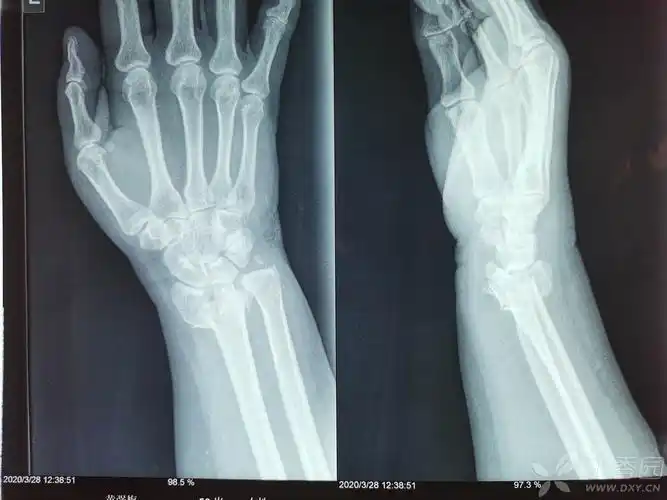

一例桡骨远端粉碎性骨折 复位前和复位后